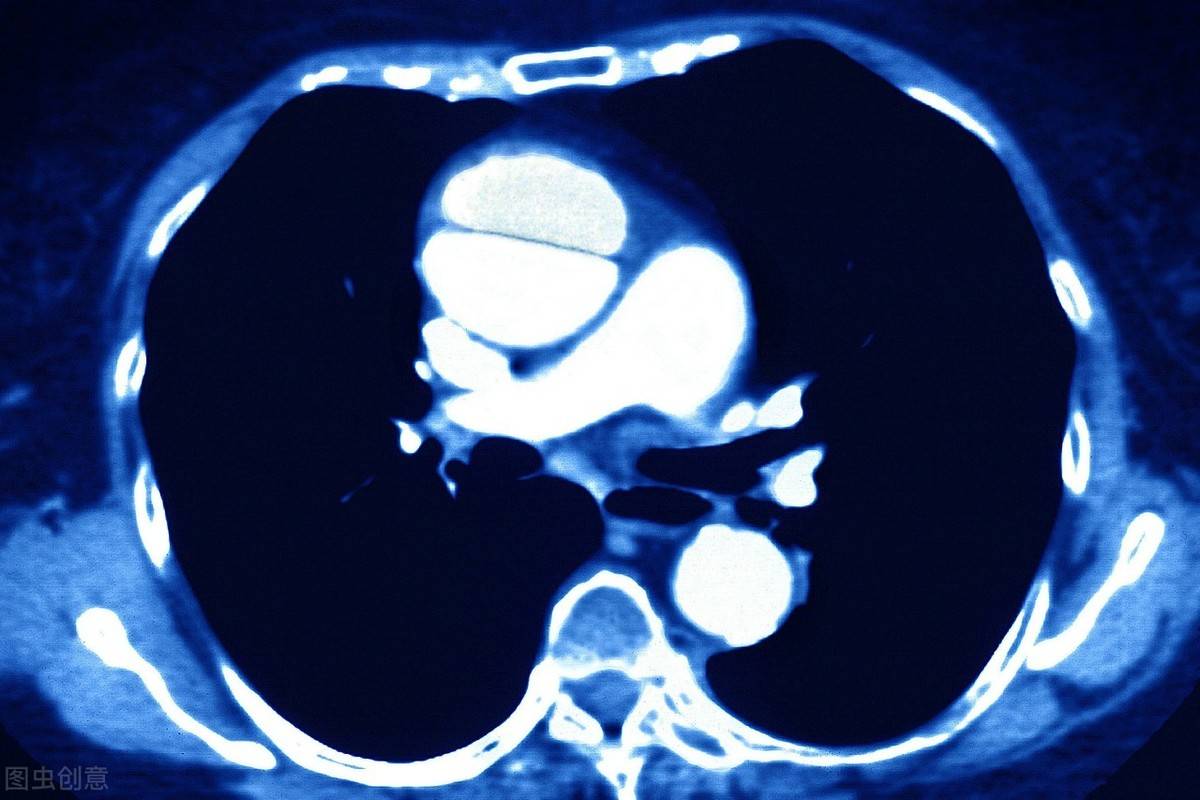

第一千零四十二章 两台手术夹层是主动脉腔内的血液从主动脉内膜撕裂或病变处进入主动脉中膜,使中膜分离,沿主动脉长轴方向扩展形成主动脉壁的真假两腔分离状态。 这种情况下,主动脉壁就会变得相当的薄,往往一个剧烈的呼吸或者喷嚏,都有可能造成主动脉破裂。 主动脉夹层在临床上本就是不太多见的病症,...

o(╯□╰)o 3种胸痛有一种致死率50%!不想冠心病猝死,5件事要做好主动脉夹层指主动脉腔内的血液从主动脉内膜撕裂处进入主动脉中膜,使中膜分离,形成主动脉壁的真假两腔分离状态。主动脉夹层分为A型和B型,其中A型死亡率更高,24小时的死亡率可达25%。 主动脉夹层的典型症状包括突发的剧烈胸痛、面色苍白等。一旦出现这些症状,应立即就医。...